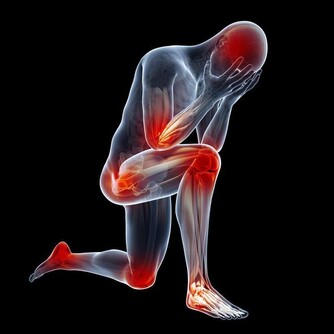

5、神經、精神障礙

有一些女性朋友在到了更年期以後,血壓會出現較為明顯的上下波動情況;絕大部分更年期女性可能有情緒不穩定、易激動、性格變化、記憶力減退等更年期綜合症症狀表現。